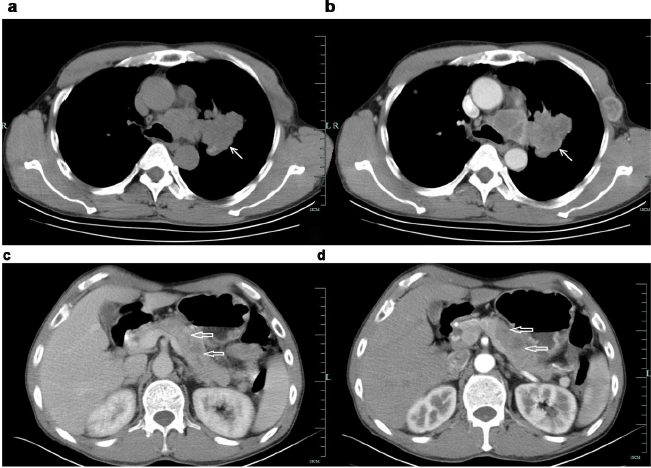

A 56-year-old male was admitted to the People’s Hospital of Suichang County on May 10, 2019 with epigastric dull pain radiating into the posterior back for more than 20 days and had no obvious aggravation and relief factors. There were no nausea or any change in bowel movement habits and weight, and no pulmonary and nerve system symptoms were observed. Some medications for gastritis were taken by him, but no effect was achieved. The patient denied previous medical history of cardiovascular disease, pulmonary disease, gastrointestinal disease, tuberculosis, and denied history of food and drug allergy. He has smoking history of 40 cigarettes/day for more than 30 years (smoking index > 1200). A 4cm*4cm mass was found in the left chest wall, with clear boundary, hard texture, and well activity. His abdomen was soft, with slight tenderness in the right upper abdomen. No enlarged systemic superficial lymph nodes were observed. No positive signs of cardiovascular system, pulmonary system and nervous system were found. Laboratory tests revealed elevated levels of carcinoembryonic antigen (CEA) 9.82ng/ml (reference range: 0-5ng/ml), and CA19-9 44.50U/ml(reference range: 0-37U/ml). Enhanced CT scan showed multiple pancreatic tumors with lymph node metastasis in the retroperitoneum. Pulmonary CT showed left lung tumor with multiple metastasis (of lung in the left chest wall and lymph nodes in the hilum, mediastinum, axilla). (Figure 1) Cranial MR suggested multiple abnormal signal nodules in both cerebellar hemispheres and considered it as metastatic.

Figure 1: Enhancement CT of the patient.

a. a&b: Irregularly lobulated uniform-density soft tissue mass was found in the lateral hilar region of the upper lobe of the left lung, with mild enhancement in enhanced scanning. Bronchial stenosis and occlusion of the upper lobe of the left lung ⬉.

b. c&d: Multiple low-density lesions in the body and tail of enlarged pancreas, with delayed enhancement in enhanced scanning. The distal pancreatic duct was slightly dilated. The local fat space was not clear, and no enlarged lymph node was observed ⇐.